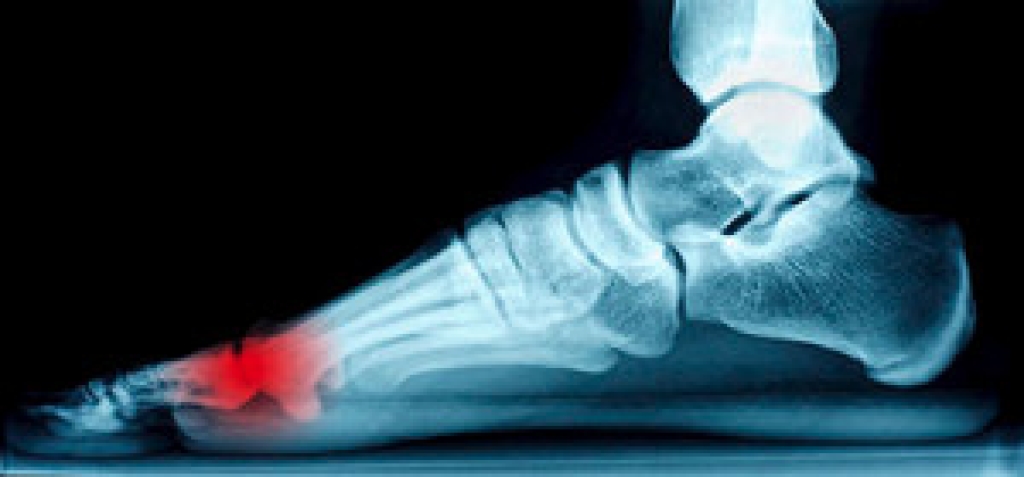

Sesamoids are tiny bones located within tendons that connect to muscles—as opposed to most bones which link to one another via joints. The patella, or kneecap, is the largest sesamoid, while the two sesamoids on the bottom of the feet near the big toe (the tibial and the fibular) are pea-sized. Despite their small size, these two sesamoids bear the body’s weight and the tendons they are attached to can become inflamed if they are overly stressed from high heels or activities such as ballet, basketball, or running. This condition is called sesamoiditis and can cause gradually-worsening pain under the ball of the foot, and popping sensations or difficulty bending the big toe. If you experience any of these symptoms, a podiatrist can thoroughly examine you and may utilize an X-ray, bone scan, MRI or ultrasound to determine if you have sesamoiditis. Treatment may involve lifestyle or footwear modifications, medications, or orthotics. Severe cases of sesamoiditis that do not respond to traditional treatment may require surgery.

Sesamoiditis is a condition of the foot that affects the ball of the foot. It is more common in younger people than it is in older people. It can also occur with people who have begun a new exercise program, since their bodies are adjusting to the new physical regimen. Pain may also be caused by the inflammation of tendons surrounding the bones. It is important to seek treatment in its early stages because if you ignore the pain, this condition can lead to more serious problems such as severe irritation and bone fractures.